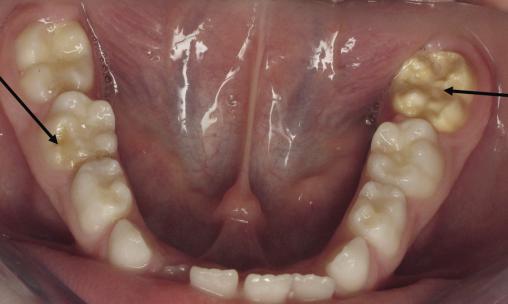

Atteinte MIH sur la dent n° 36 (première molaire permanente mandibulaire gauche) et HSMP sur la dent n° 85 (deuxième molaire temporaire mandibulaire droite).